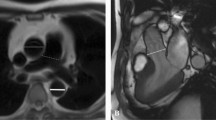

All measurements were performed on a cardiovascular imaging workstation (Circle CVI42; Circle Cardiovascular Imaging Inc. Alberta, Canada) after studies were anonymized. All images were visualized in axial, sagittal, and coronal planes with a window (600–900) and a level (250–350) settings. Double-oblique planes were obtained using multiplanar reformatting to measure MPA midway between the pulmonary valve and PA bifurcation. The proximal branch PAs were measured immediately after the PA bifurcation, all measures were made en face [20, 29]. Maximum, minimum, and mean diameters and cross-sectional area for MPA and branch PAs by planimetry were measured (Fig. 1). The measurements were categorized as either systolic or diastolic as described above.